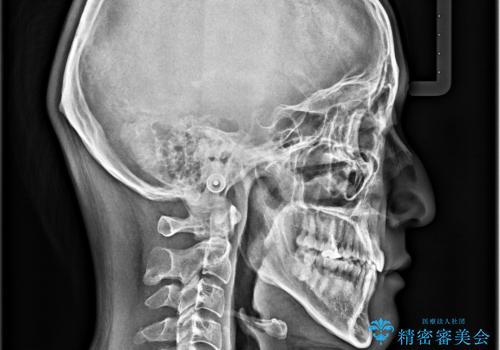

ガタガタの歯並び、八重歯をなおしたい、骨格性下顎前突 カモフラージュ矯正

骨格的に上顎骨が小さいために相対的に下顎骨が前に出ていたため、歯の傾きなど理想的な仕上がりが難しく、外科矯正ではなく歯列矯正の場合はカモフラージュ矯正になること説明の上、矯正治療を進めることになりました。

上顎は左右5番抜歯、下顎は左右4番抜歯しています。